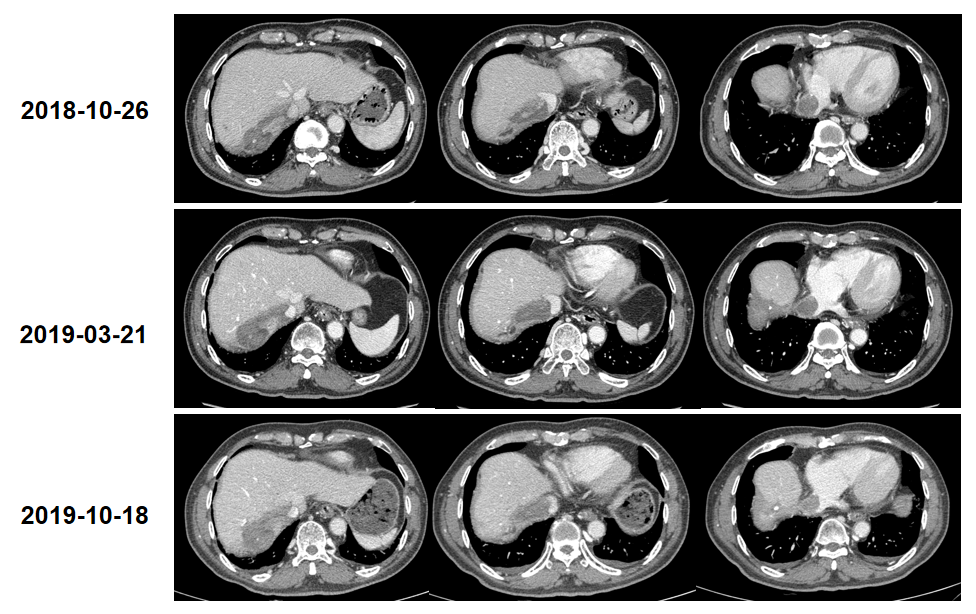

继续口服阿帕替尼500mg,规律复查,癌栓稳定,未见强化(图6)。

Child-Pugh A级肝癌切除术后复发患者,行TACE联合MWA治疗后PFS达22.3个月。后患者病灶周围复发,同时合并肝静脉、下腔静脉及右心房癌栓,行TACE联合阿帕替尼治疗后,病灶、癌栓坏死退缩;患者继续口服阿帕替尼维持治疗,癌栓达稳定状态。值得一提的是,患者下腔静脉栓塞(血供减少,但并未坏死),予阿帕替尼治疗后,癌栓完全没有强化,这在临床中极为少见。目前患者生活质量佳,阿帕替尼可观ORR带来的整体疗效值得肯定。